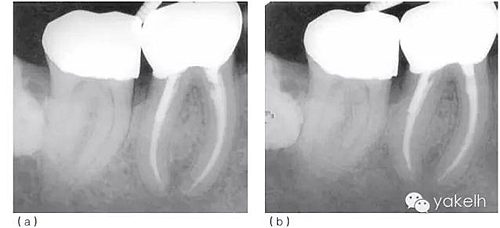

術(shù)后觀察愈合情況。最后制作新的樁冠。術(shù)后2年、6年復(fù)查,X線片顯示根尖周病損逐漸恢復(fù)(圖5.1.3)。

圖 5.1.3(a)根管再治療后2年復(fù)查,X線片顯示46根尖周骨重建、遠中根管內(nèi)金屬樁、金合金冠修復(fù)。(b)根管再治療后6年復(fù)查,X線片顯示46根尖周完全恢復(fù)。